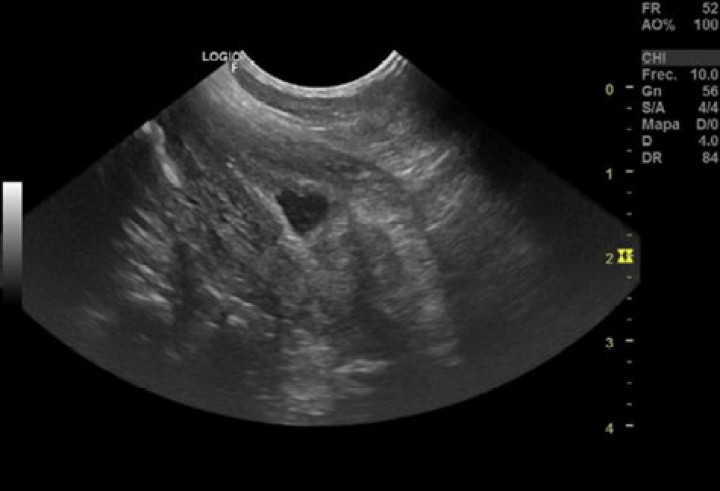

Los resultados de la analítica sanguínea estaban dentro de la normalidad, con excepción de una uremia leve (30 mg/dl; valor de referencia: 7-27 mg/dl). El estudio radiográfico y ecográfico abdominal solo evidenció un foco hiperecoico con un cono de sombra acústica asociado a la unión corticomedular del riñón derecho compatible con una posible calcificación (Fig. 1). La vejiga no pudo ser valorada al presentarse vacía, no pudiéndose realizar cistocentesis para hacer cultivo de orina (Fig. 2).

<p>Imagen de un corte sagital del riñón derecho, en el que puede apreciarse una estructura hiperecogénica en la zona de la pelvis renal.</p>

Figura 1

Imagen de un corte sagital del riñón derecho, en el que puede apreciarse una estructura hiperecogénica en la zona de la pelvis renal.

Los propietarios cancelaron la cita de la revisión debido a factores personales y a la mejoría de la sintomatología clínica. Dos días después la hematuria del paciente empeoró drásticamente y acudieron a la consulta. En ese momento se repitió la ecografía abdominal, evidenciándose una vejiga distendida con una pared vesical engrosada y la aparición de una estructura lineal intraluminal compatible con un cuerpo extraño vesical (Fig. 3). Se realizó una cistocentesis y se remitió la muestra para hacer un urocultivo.

<p>(<strong>A</strong>) Imagen ecográfica de un corte sagital de la vejiga, apreciándose una estructura ramificada hiperecogénica con aspecto de espiga en su interior. (<strong>B</strong>) Imagen ecográfica de un corte sagital de la vejiga, apreciándose desde otro ángulo la estructura hiperecogénica ramificada compatible con cuerpo extraño de origen vegetal (espiga).</p>

Figura 3

(A) Imagen ecográfica de un corte sagital de la vejiga, apreciándose una estructura ramificada hiperecogénica con aspecto de espiga en su interior. (B) Imagen ecográfica de un corte sagital de la vejiga, apreciándose desde otro ángulo la estructura hiperecogénica ramificada compatible con cuerpo extraño de origen vegetal (espiga).

A las 48 horas de la intervención el paciente no presentaba ningún tipo de sintomatología urinaria y el aspecto ecográfico de la vejiga presentaba un engrosamiento moderado/leve de la pared vesical debido a la propia cistotomía ventral.